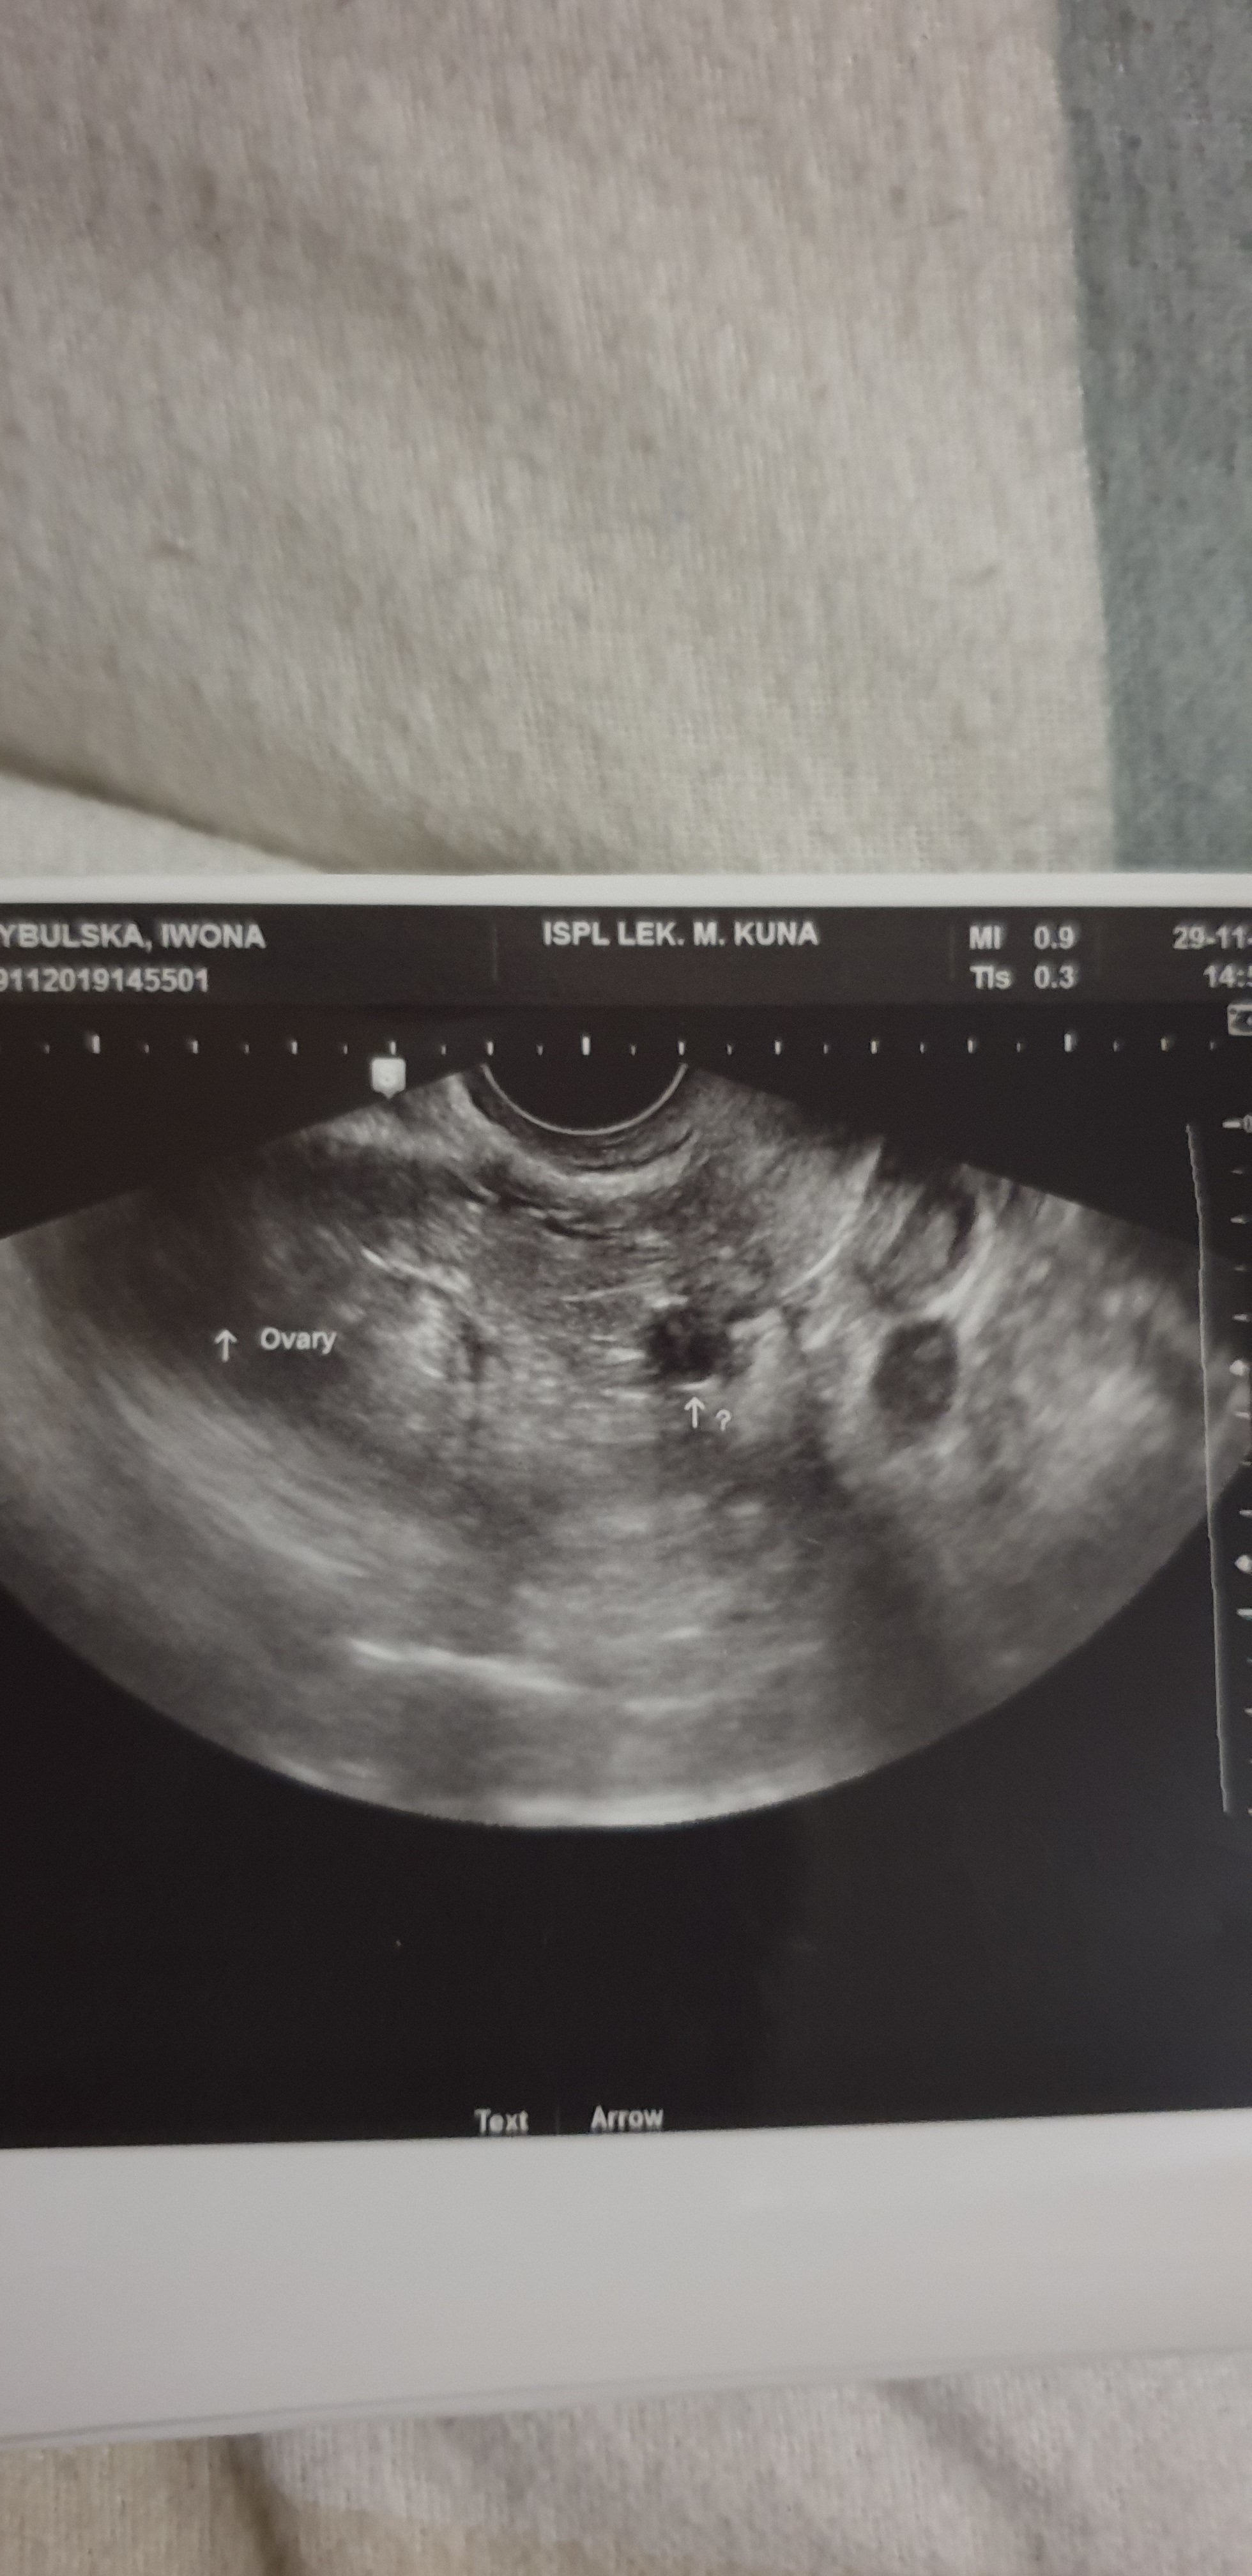

No i mone szczescie nie trwalo dlugo. Dzis beta tylko 628. Bylam u lekarza cos znalazl ale do konca nie wie co to jest. Znowu z prawej strony. Czy to jest mozliwe? W tym samym jajowodzie? I czy jest szansa ze przy takiej becie cos widzial?

A beta przyrasta ? Przy takiej wartości to niewiem czy coś widać . Ja miałam bete 688 i gin tylko podejrzewała ze jest pozamaciczna . Po 24 h moja beta 1001 i już było widać ze jest w jajowodzie

To moje usg...

• 20191129_175719.jpg